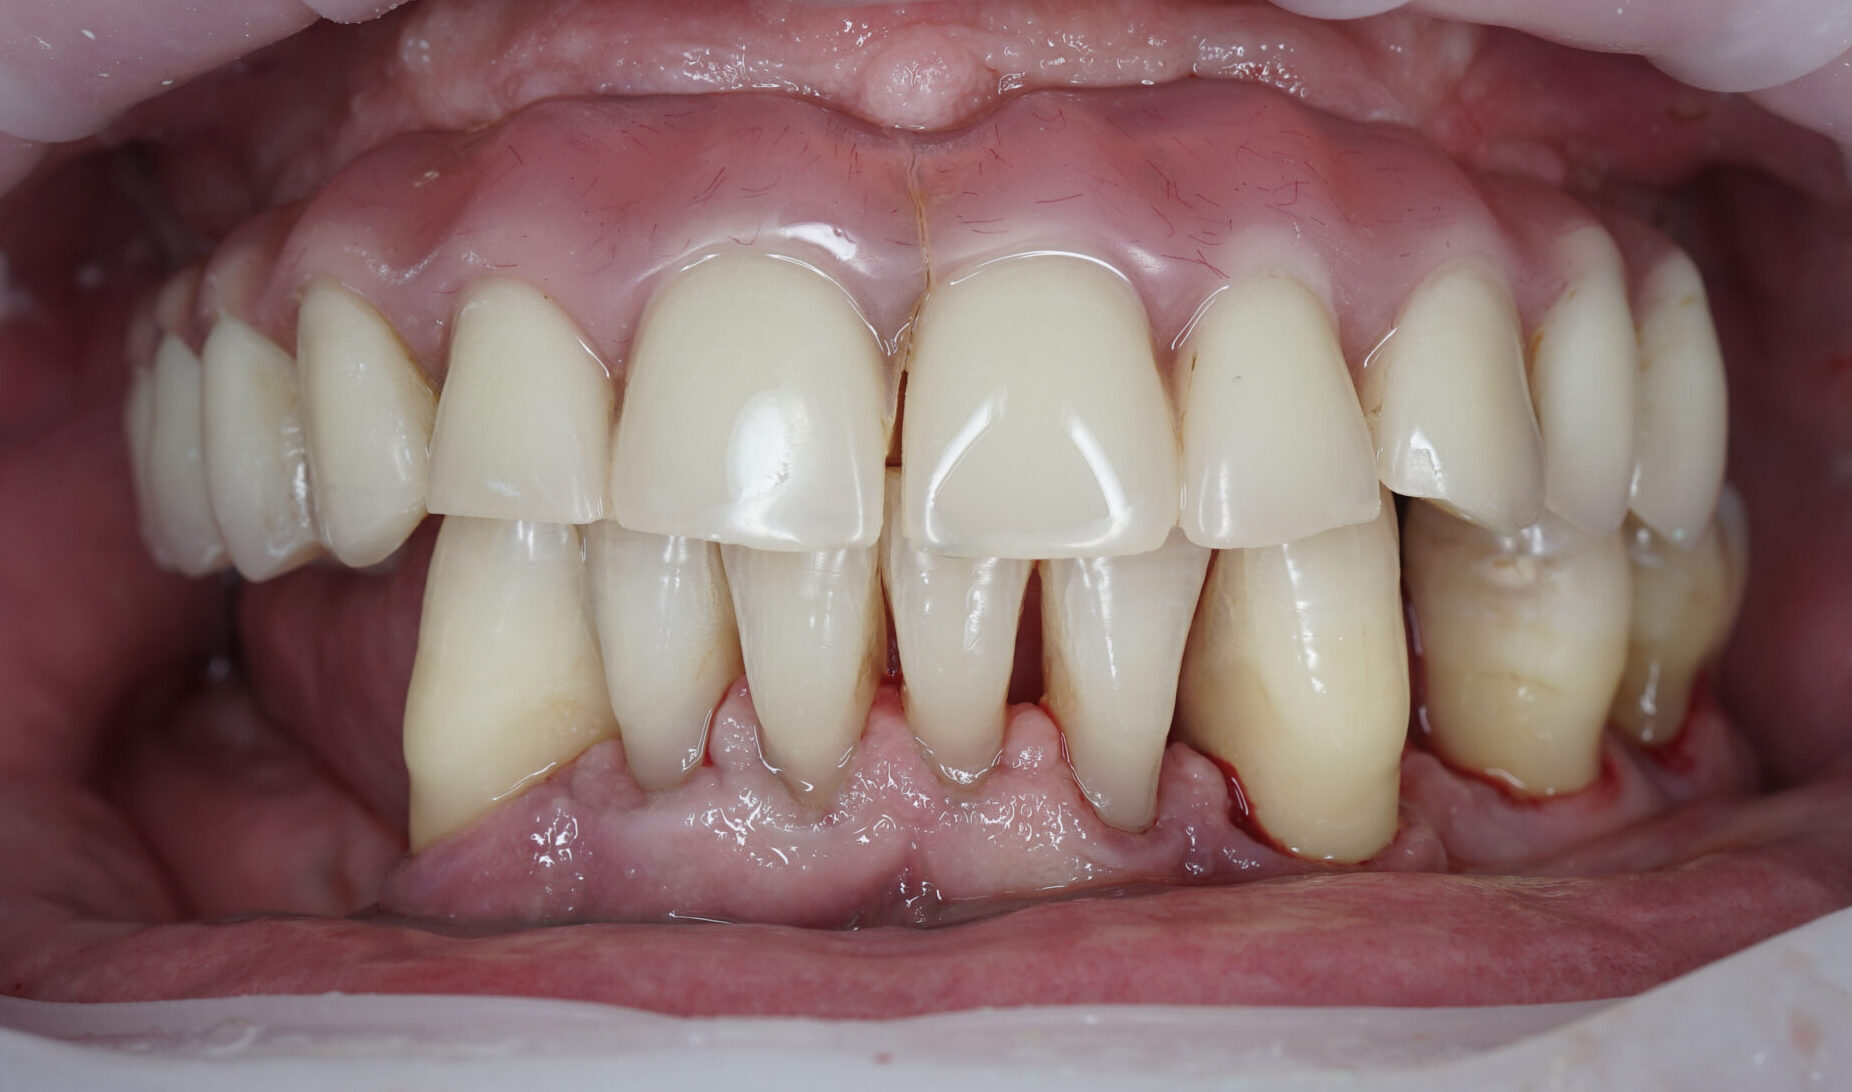

Примеры наших работ